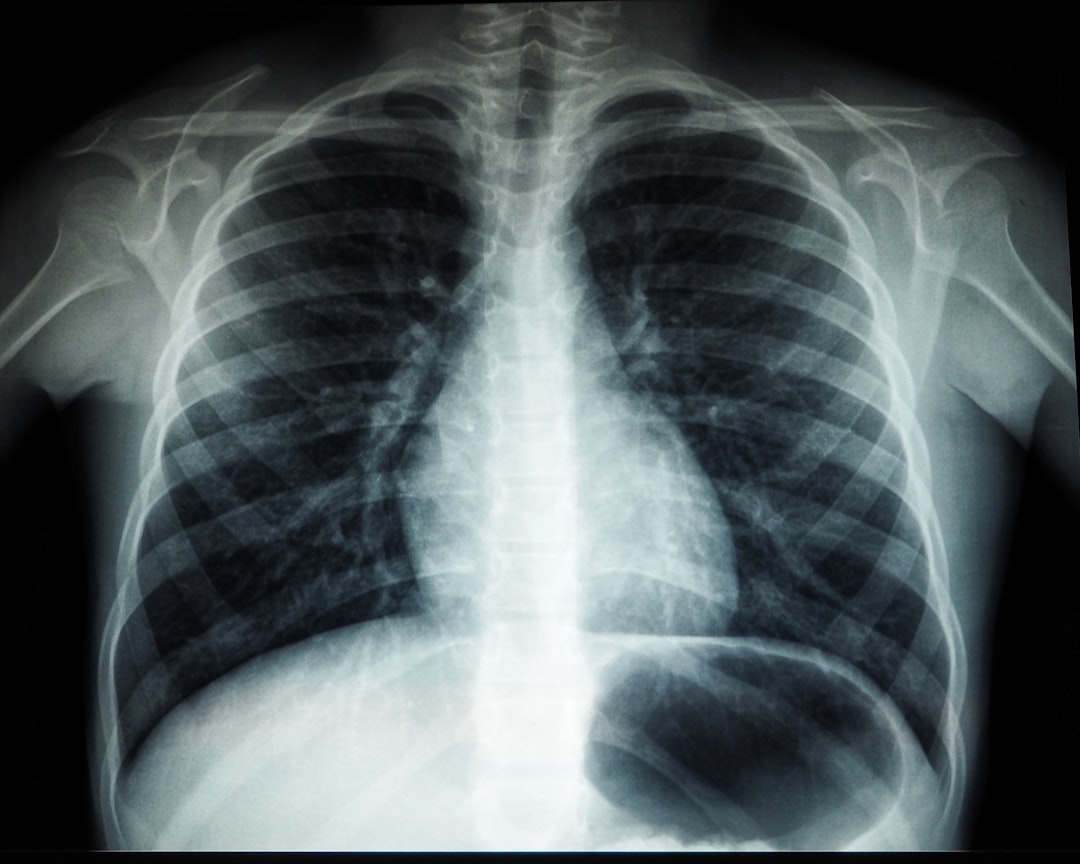

폐렴 초기증상은 시작할 때 신체에서 보내는 중요한 신호입니다. 대개 감기나 독감으로 잘못 생각할 수 있지만, 폐렴 초기증상이 지속되면 즉시 의사의 진료를 받아야 합니다. 가장 많이 나타나는 증상으로는 기침, 가벼운 숨쉬기 어려움, 가슴 통증 등이 있습니다. 이런 증상들이 지속되면 무시하지 말고 전문가와 상담하세요. 특히, 체력에 따라 증상의 강도가 달라질 수 있습니다.

기침은 기침을 통해 체내의 이물질이나 세균을 제거하려는 자연스러운 과정입니다. 그러나 폐렴에서의 기침은 일반적으로 마른 기침부터 시작해 점차 피가 섞인 가래가 나올 수 있습니다. 폐렴 초기증상이 심해질 경우 고열이 동반될 수 있으며, 체온이 39도 이상으로 오르면 더욱 주의가 필요합니다. 이럴 땐 병원으로 꼭 가야 합니다!

또한, 숨 쉬는 것이 힘들게 느껴지면 신체가 산소 부족 상태에 놓일 수 있다는 신호입니다. 이런 상황에서는 자세를 바꿔보거나 공기가 잘 흐르는 곳으로 이동하는 것이 좋습니다. 만약에도 증상이 계속된다면, 폐렴 초기증상을 가볍게 여기지 말고 전문의의 진료를 받는 것이 중요하다고 강조하고 싶습니다.

마지막으로, 가슴 통증이 느껴진다면, 이는 폐렴증상이 진행되고 있다는 신호일 수 있습니다. 이 통증이 심해질 경우에는 바로 진료를 받아야 합니다. 폐렴 초기증상을 발견하는 것이 조기 치료의 열쇠임을 기억하세요! 그러니, 예전에는 저에게 이런 일이 없었는데 하고 놀라움을 느낄 수도 있습니다. 다가올 이야기들을 들어보세요!